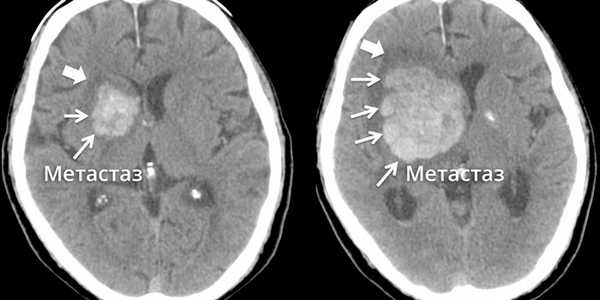

С помощью КТ также можно выявить метастазы, однако этот метод уступает МРТ при обследовании инфратенториальной области и ствола мозга.

Менингеальный карциноматоз у пациента с доказанным метастазом бронхиальной аденокарциномы. Кистозный, с центральной гиподенсной зоной метастаз рака молочной железы, который может быть принят за глиобластому.. Метахронные метастазы колоректального рака с сопутствующими крупными и мелкими очагами. Аденокарцинома легких с кистозным симптоматическим метастазом в правой височной доле, выявленным на КТ (вверху слева), а также МРТ (вверху справа).

Инфратенториальный очаг гораздо лучше визуализируется на МРТ. Метастаз в пинеальную область с угрожающей окклюзионной гидроцефалией

и компрессией четверохолмной пластинки, который может быть легко резецирован. Диффузное поражение, которые не оставляет терапевтической возможности.